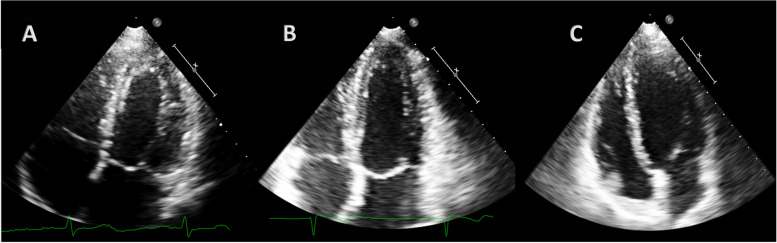

Methods: 21 female elite athletes (23.2 ± 5.3 years), 25 women with twin pregnancies (35.4 ± 5.7 years) and 25 healthy competitive female athletes (controls), age-matched with pregnant women (34.9 ± 7.9 years), were enrolled. This latter group was included to minimize the effect of age on cardiac remodeling. All women evaluated through anamnestic collection, physical examination, 12 leads ECG, standard echocardiogram and strain analysis. Sphericity (SI) and apical conicity (ACI) indexes were also calculated.

Results: Pregnant women showed higher LA dimension (p < 0.001) compared to both groups of athletes. LV e RV GLS were significantly different in pregnant women compared to female athletes (p = 0.02 and 0.03, respectively). RV GLS was also different between pregnant women and controls (p = 0.02). Pregnant women showed significantly higher S' wave compared to female athletes (p = 0.02) but not controls. Parameters of diastolic function were significantly higher in athletes (p = 0.08 for IVRT and p < 0.001 for E/A,). SI was lower in athletes in both diastole (p = 0.01) and systole (p < 0.001), while ACIs was lower in pregnant women (p = 0.04).

Conclusions: Cardiac remodeling of athletes and pregnant women could be similar at first sight but different in LV shape and in GLS, highlighting a profound difference in longitudinal deformation between athletes and pregnant women. This difference seems not to be related with age. These findings suggest that an initial maternal cardiovascular maladaptation could occur in the third trimester of twin pregnancies.